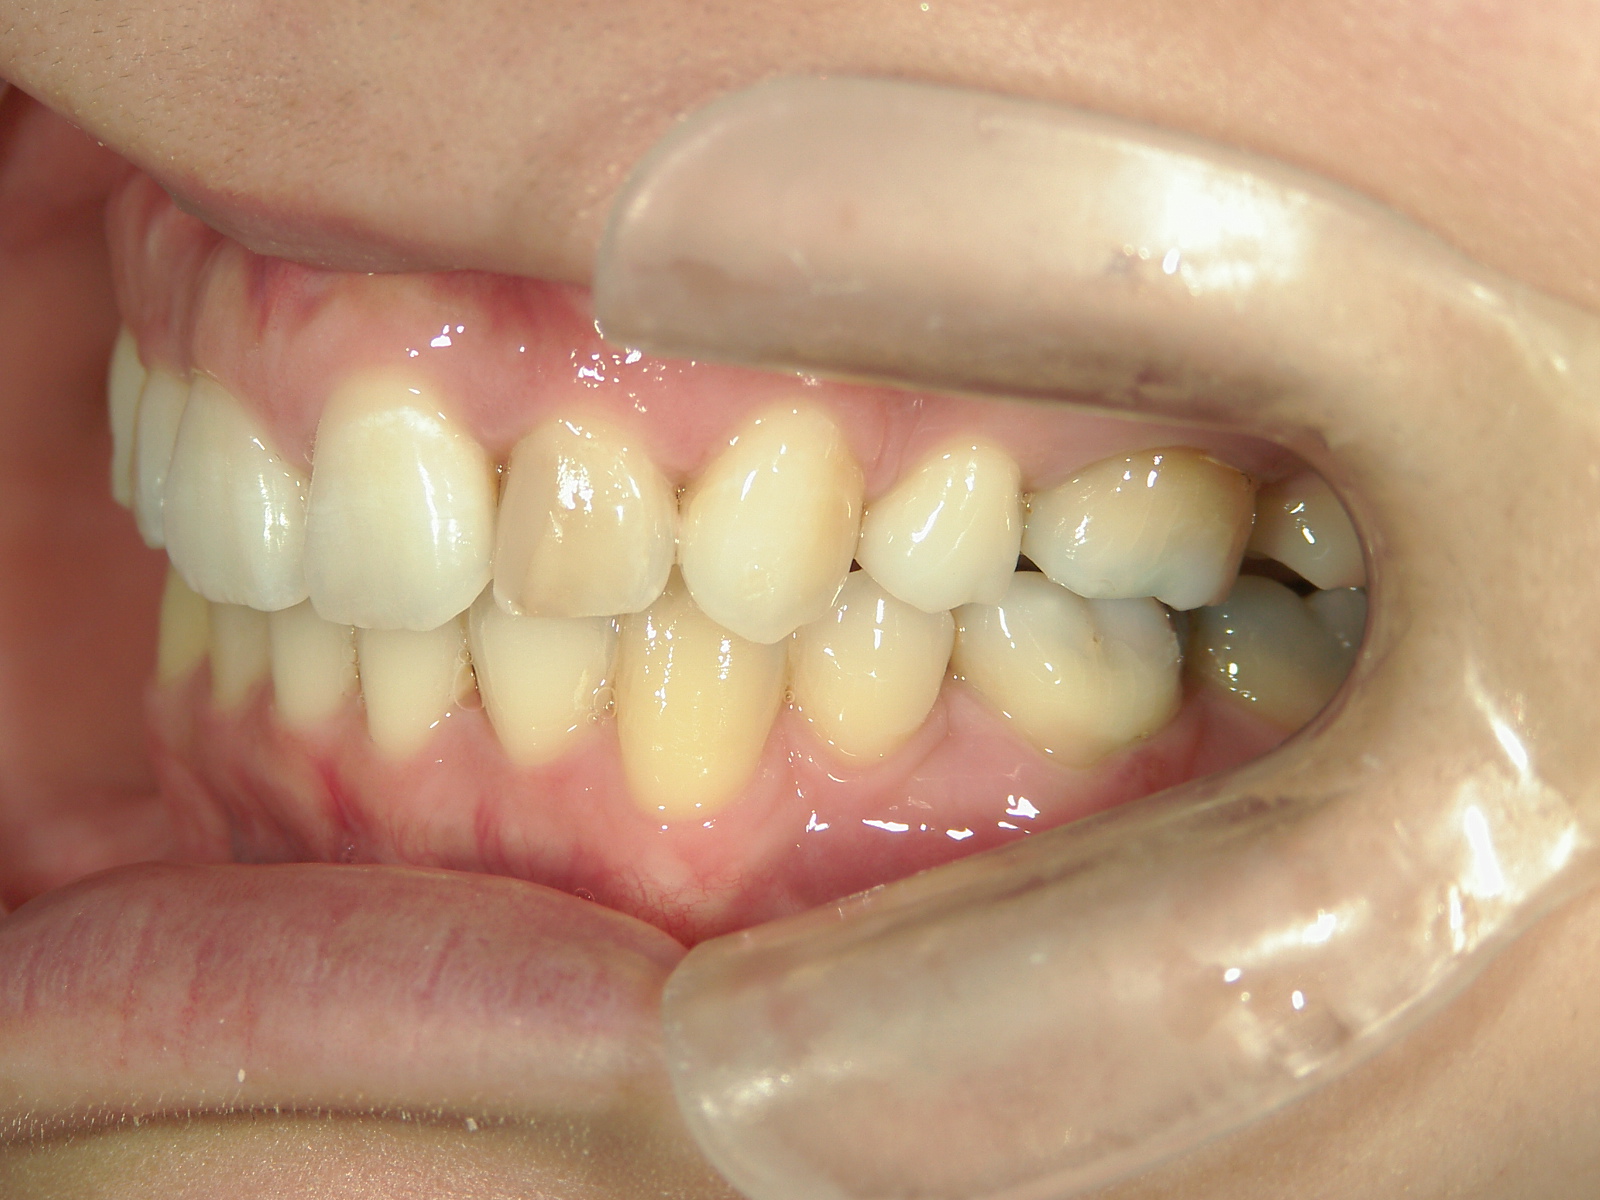

舌側ワイヤー矯正 症例(25)

主訴: 歯並びが気になる

カテゴリー : ガタガタ(叢生)